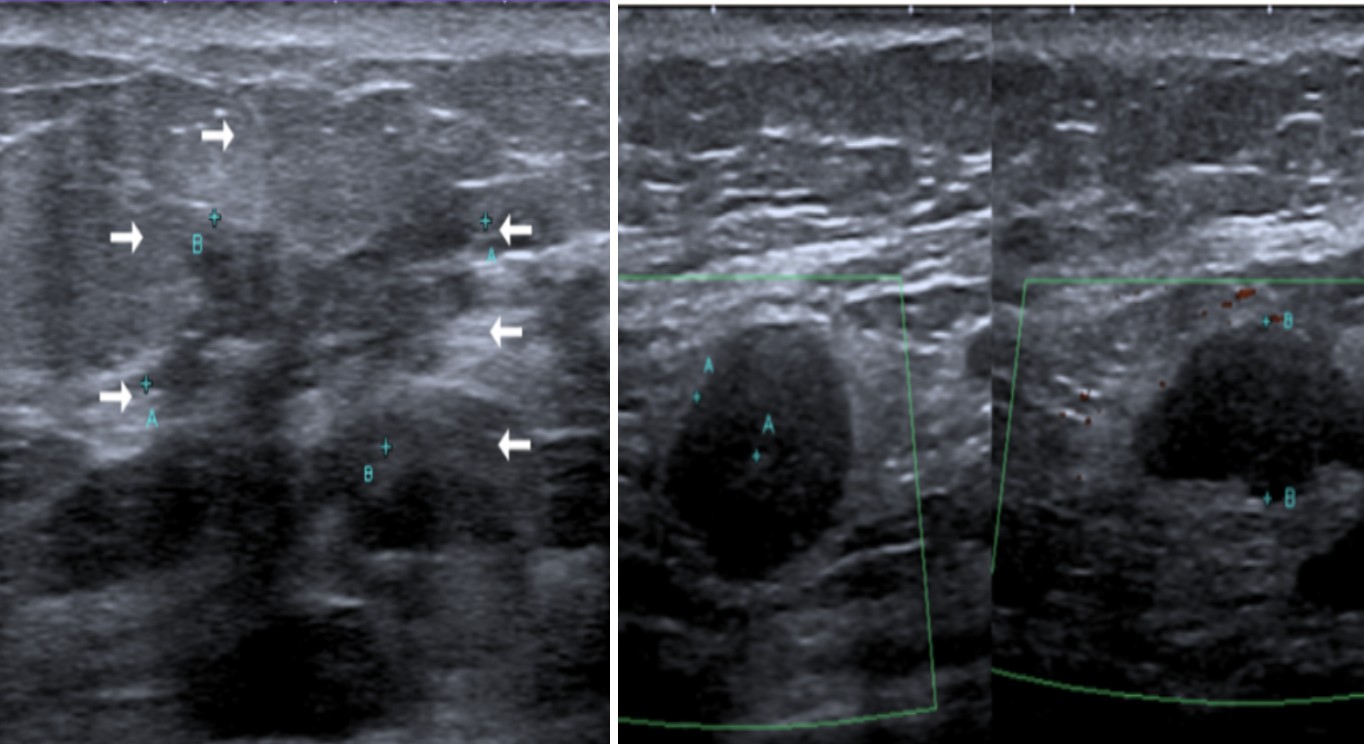

Al ultrasonido se evidenció lesión no masa, hipoecoica, hipervascular al Doppler color, con calcificaciones, localizada CSE, R9 a R12, asociado a nódulos adyacentes; al menos cuatro, también se observaron cuatro adenopatías BRN4 en nivel axilar I derecho (Fig 2.).

Figura 2. Ultrasonido: Lesión no masa, hipoecoica, hipervascular al Doppler color, con calcificaciones, localizada en CSE, R9 a R12, con nódulos adyacentes y adenopatías BRN4 en nivel axilar I derecho.